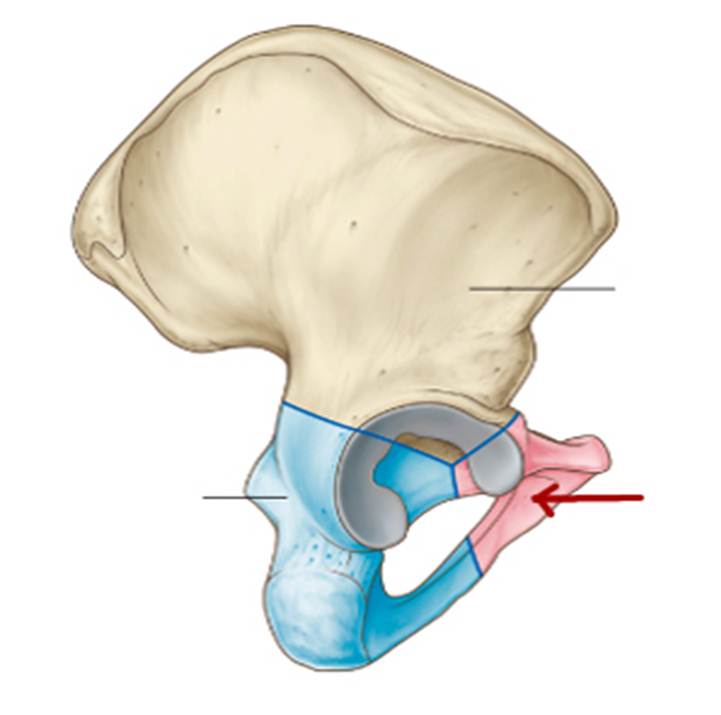

S: На рисунке обозначен art. Coxae (латинский язык).

S: Стрелка указывает на zona orbicularis

S: Стрелка указывает на lig. Ischiofemorale

S: Стрелка указывает на lig. pubofemorale

S: Стрелка указывает на labrum acetabuli

S: Стрелка указывает на lig. Capitis femoris

S: Стрелка указывает на facies lunata